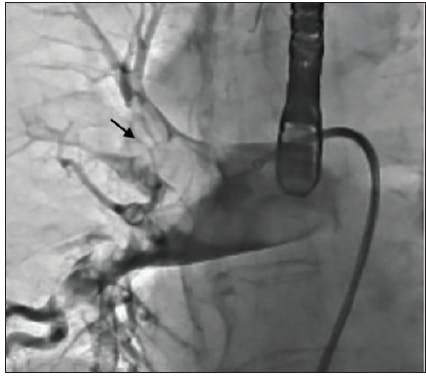

The initial angiogram confirmed an occlusion with extensive thrombus burden of a dominant left circumflex artery and TIMI 0 flow (Figure 1). Power aspiration with CAT RX and Penumbra ENGINE was started after wiring the dominant left circumflex artery. After one pass with CAT RX, the initial occlusion was removed. A second angiogram showed extensive clot burden spread across multiple branches (Figure 2). Each vessel was wired sequentially, delivering power aspiration via CAT RX to the site of each thrombus. A final angiogram revealed complete reperfusion to the dominant left circumflex artery and branches, with TIMI 3 flow (Figure 3).

Manual aspiration using a Pronto V3 (Teleflex) catheter restored some flow, however, distal embolization to the posterior descending artery (PDA) immediately caused right ventricular cardiac arrest (Figure 2). The patient underwent six shocks and was intubated while CAT RX was delivered through the freshly placed 3.5- X 38-mm DES to the PDA. Two passes of CAT RX with the Penumbra ENGINE resulted in TIMI 3 flow restoration and retrieval of the distal emboli from the PDA (Figure 3). The patient’s symptoms normalized, the electrocardiogram stabilized, and the acute MI was immediately resolved. The patient remained on cangrelor with no need for tirofiban.